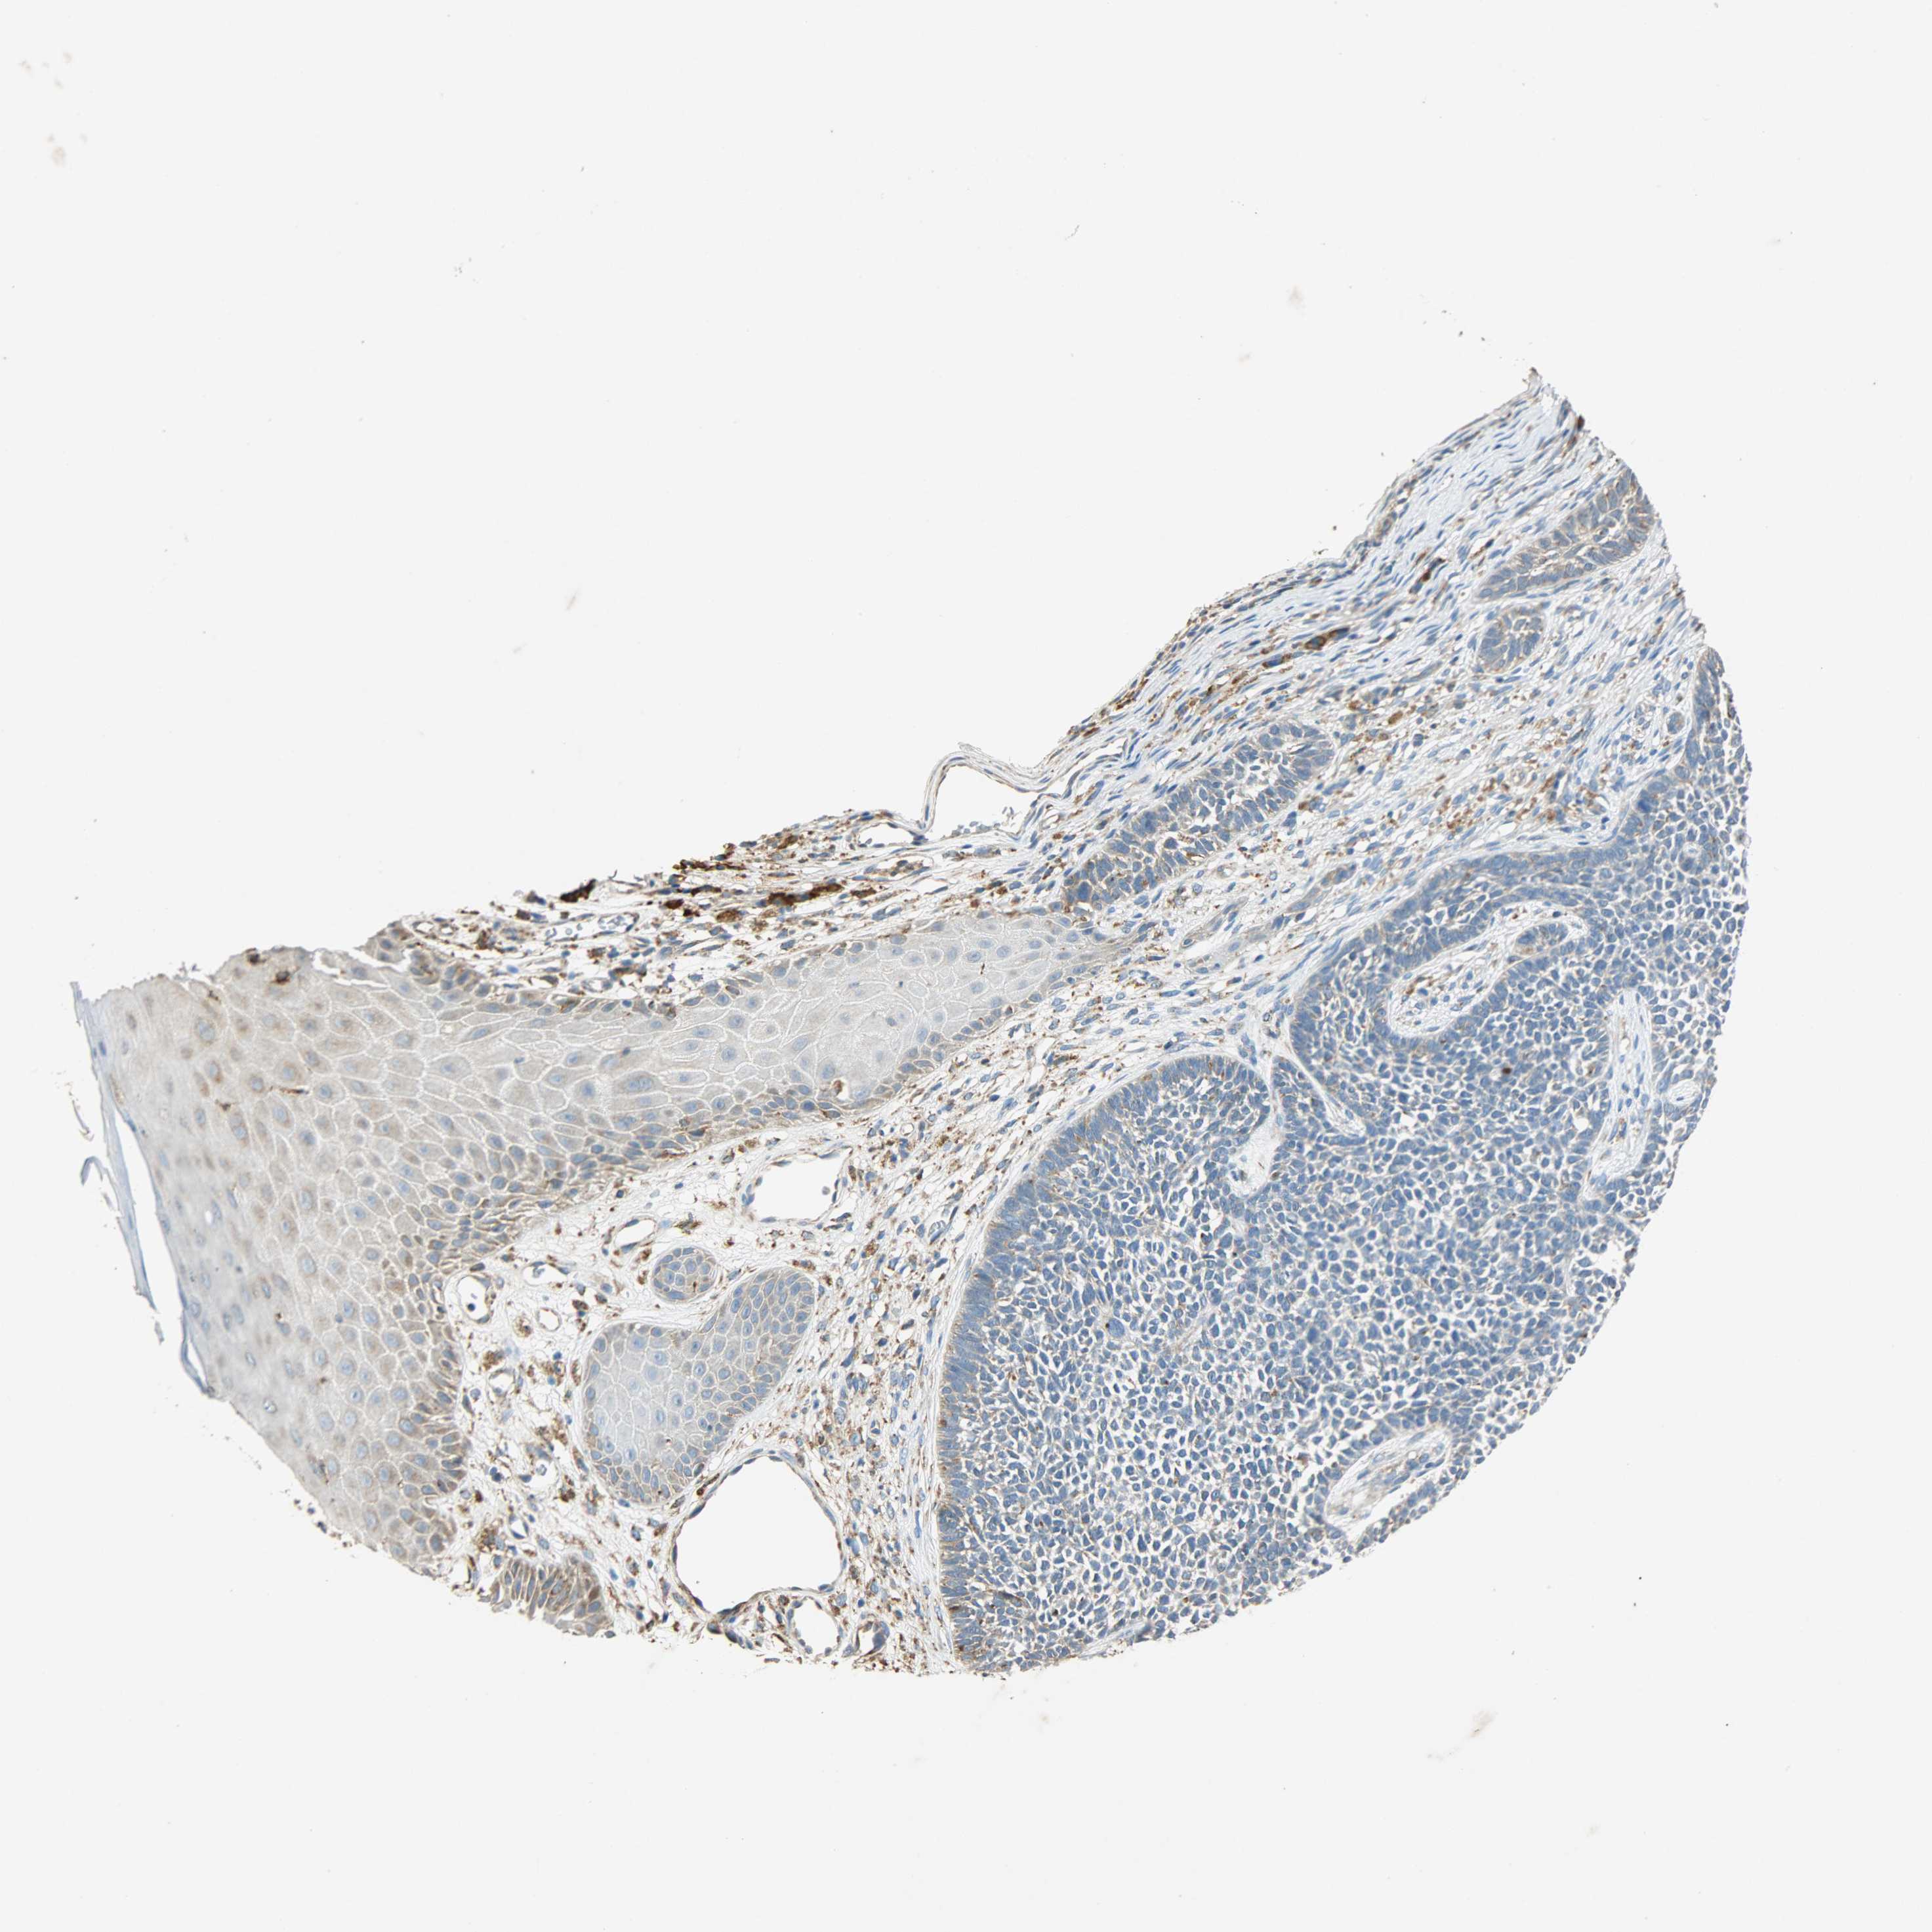

Basal cell and squamous cell cancer

SKIN CANCER - Protein expressioni

A mouse-over function shows sample information and annotation data. Click on an image to view it in a full screen mode. Samples can be filtered based on level of antibody staining by selecting one or several of the following categories: high, medium, low and not detected. The assay and annotation is described here.

Each image is clickable and will lead to virtual microscopy that enables deeper exploration of all samples and also displays staining intensity scores, fraction scores and subcellular localization as well as patient and tissue information for each sample.

Antibody HPA038845

Antibody HPA038846

Antibody CAB005221

Squamous cell carcinoma, NOS

Squamous cell carcinoma, metastatic, NOS